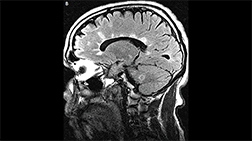

Typical lesions of multiple sclerosis are found in the juxtacortical.

Confluent lesions may appear later in the course of multiple sclerosis.

Cortical, juxtacortical lesions, and U-fiber lesions. Arrows: multiple small juxtacortical and cortical lesions throughout cerebral hemispheres. By definition, no white matter may interpose between a juxtacortical lesion and the cortex. Note U-fiber lesions along arcuate fibers in middle left frontal lobe, highly characteristic of demyelination and not seen in normal aging or vascular disease.